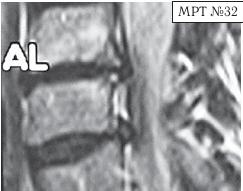

МРТ № 31 ![]() Он взял отпуск и поехал в Москву в довольно известную частную клинику. Прошёл курс лечения, который включал в себя «стандартный набор»: — мануальную терапию, с целью уменьшения (устранения) болевого синдрома, путём восстановления соотношений суставных поверхностей дугоотростчатых суставов в сегментах CV-CVI и CVI-CVII (устранение сублюксации); — массаж шейного отдела позвоночника (для расслабления мышц, улучшения кровообращения); — физиотерапию — магнитотерапию, инфракрасный лазер на воротниковую зону, с целью уменьшения воспалительных процессов и отёчности в поражённых тканях; — медикаментозную терапию — стандартный набор нестероидных препаратов, витамины и анальгетики; — физические упражнения на тренажёрах и лечебная физкультура для укрепления мышечного корсета позвоночника и выработки правильной осанки, придание связочно-мышечному аппарату необходимой гибкости с целью увеличения объёма движений в позвоночнике. После лечения действительно почувствовал себя лучше, работоспособность была восстановлена. Но, чтобы не утратить достигнутый результат лечения, следуя рекомендациям, полученным в московской клинике, он продолжил заниматься на тренажёрах. Даже приобрёл несколько универсальных (многофункциональных) тренажёров. Один установил дома, другой — на работе. Жизнь вошла в привычное русло. Боли в шее периодически возникали, но проходили после занятий на тренажёре. К медикаментам прибегал в редких случаях. Так продолжалось практически год, пока не появилась боль в левой руке и онемение IV и V пальцев. Занятия на тренажёре только усиливали боли, а лекарства практически не действовали. В связи с чем он был вынужден опять обратиться в ту же клинику. После лечения (практически по той же схеме) боли уменьшились, но полностью не прошли, онемение усилилось. Через некоторое время появилась субфебрильная температура (37–37,2 °C), общая слабость, частые головные боли, головокружения. По жалобам и ощущениям с его слов: «На голову надели будто тесную шапку и она сдавливает. А в голове туманность какая-то, мысли путаются, на чём-то сосредоточиться практически невозможно. Порой забываю, что минуту назад делал. Такое ощущение, что в голове полно посторонних мыслей: только от одних отделаюсь, как появляются другие» и так далее. Естественно, он вынужден был опять обратиться в медицинское учреждение, где ему повторно сделали МРТ (№ 32). ![]() После обследования у него было обнаружено: — абсолютный стеноз спинномозгового канала шейного отдела позвоночника с полным блоком ликворных путей и сдавлением дурального мешка спинного мозга на уровне сегментов CV-CVI и CVI-CVII; — в сегменте CV-CVI — значительный спондилёз, гипертрофия задней продольной связки, и практически компенсированная спондилёзом грыжа межпозвонкового диска; — в сегменте CVI-CVII — довольно активная грыжа межпозвонкового диска; — на уровне поражённых сегментов выраженный эпидурит. После данного обследования, когда врачи увидели грыжи межпозвонковых дисков, да и то, что происходило у пациента в шейном отделе позвоночника, они стали категорически настаивать на немедленной операции. Однако перспектива стать инвалидом на всю оставшуюся жизнь явно не прослеживалась в планах пациента. Когда прозвучали два слова — «грыжи» и «операция», этот человек, естественно, тут же вспомнил и про меня, и про нашу давнишнюю с ним дружбу. Однако меня не удовлетворили результаты его обследования. Если бы дело было только в грыжах, это полбеды. Меня смущало наличие других симптомов, которые косвенно свидетельствовали о возможном поражении ЦНС. Поэтому я послал его на дополнительные обследования МРТ головного мозга (№ 33), тесты (ИФА (иммуноферментный анализ), ПЦР (Полимеразная Цепная Реакция на инфекции), которые дали положительный результат на герпесвирусы: Epstein-Barr virus (EBV) (вирус Эпштейна-Барр) и Cytomegalovirus (CMV) (вирус Цитомегаловирус). МРТ № 33

МРТ № 33 На МРТ отчётливо видны множественные очаги демиелинизации, вследствие развития нейроинфекции Этот случай очередной раз указывает на то, как даже гениальный мозг может пострадать от банальной глупости человеческой. Есть такие замечательные слова древнекитайского философа Лао-Цзюнь (Лао-Цзы) в «Рассуждениях о ста заболеваниях»: «Человек мудрости… избавляется от беды, когда она ещё не появилась. Ведь катастрофа рождается из мелочей, а болезнь возникает из тончайших отклонений». Грыжа Шморля Некоторых моих пациентов интересует вопрос, что такое грыжа Шморля, которая у них была обнаружена в результате обследования. Грыжа Шморля (хрящевой узелок Шморля, узелок Шморля) — это медицинский термин, который означает грыжевидное выпячивание, внедрение хрящевой ткани из межпозвонкового диска в губчатую кость тела позвонка. Названа она так в честь выдающегося немецкого патологоанатома, учёного, профессора Кристиана Шморля (Schmorl Ghristian Georg; 1861–1932), который первым описал данную патологию в рамках научного понимания начала XX века. За последние годы жизни учёный написал ценные работы по патологической анатомии позвоночника. В них профессор Шморль поделился рядом своих открытий, касающихся межпозвонковых дисков. В том числе там было описано состояние межпозвонкового сегмента, при котором межпозвонковым диском была продавлена замыкательная (гиалиновая) пластинка, отделяющая губчатую кость тела позвонка от межпозвонкового диска. Очаги данной патологии могут появиться у человека ещё в детском, подростковом возрасте. Как правило, они не имеют клинических проявлений, поэтому человек не чувствует каких-либо болевых ощущений. Но и здесь бывают свои исключения. На МРТ № 34 наблюдаются грыжи Шморля (обратите внимание на локализацию пульпозных ядер межпозвонковых дисков), при которых пациент не испытывает болевых ощущений. Данные грыжи опасений не вызывают. А вот на снимке МРТ № 35 наблюдаются грыжи Шморля с глубоким проникновением межпозвонковых дисков в тела позвонков со значительным разрушением последних. Это уже опасно. Тем более что у пациента остеопороз (дистрофия костной ткани, в результате которой кости становятся хрупкими и ломкими), что означает неизбежное прогрессирование данной патологии. А это, в свою очередь, увеличивает риск возникновения патологических переломов тел позвонков в местах развития грыж Шморля. Но не всё так уж и печально для данного пациента: если подлечить остеопороз, да в последующем бережно относиться к своему здоровью, то есть ещё шанс избежать серьёзных осложнений этого заболевания позвоночника. |